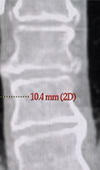

A Quantitative Assessment of Lung Tumor Motion under Abdominal Compression using 4D-CT Imaging

Stereotactic Body Radiation Therapy (SBRT) has rapidly emerged as a curative procedure for early stage non-small cell lung cancer (NSCLC). The ablativ... Read more